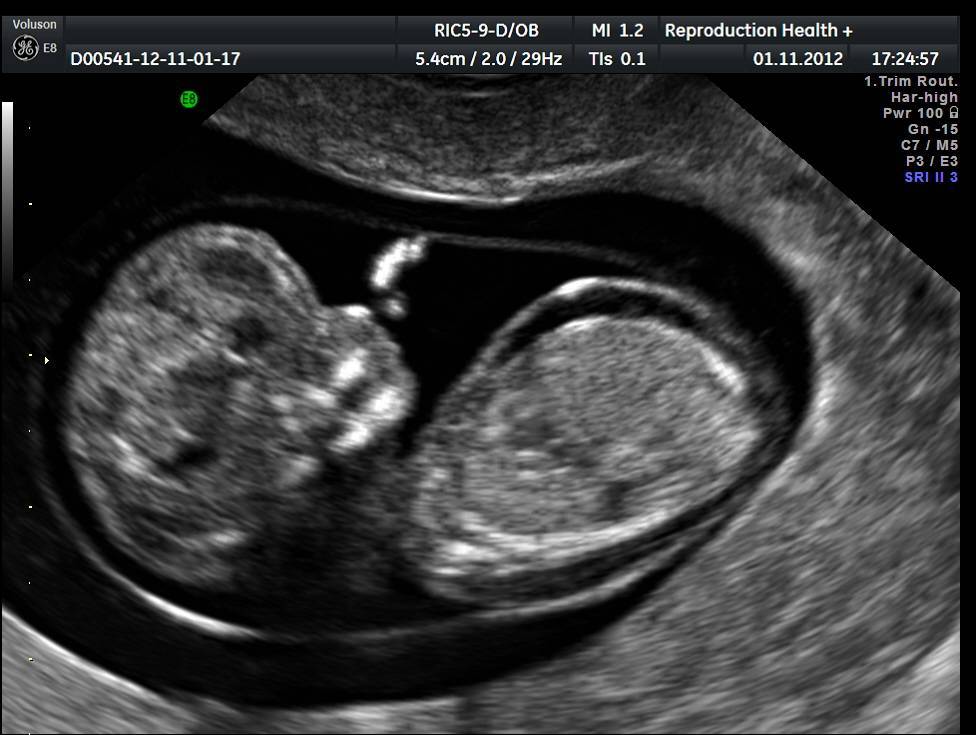

На 12 неделе эмбриональный период оканчивается, перетекая в плодный. Можно визуализировать внутренние органы, костные структуры, прослушать сердцебиение, узнать половую принадлежность. В это время у ребёнка активно формируются лицевые кости, уши, глазницы, подбородок, зачатки молочных зубов, поэтому на УЗИ (ультразвуковом исследовании) их можно чётко рассмотреть.

1. Ниже на УЗИ мы видим нормальную носовую кость. Можно различить 3 четкие линии.

2. Гипоплазия носовой кости. УЗИ сделано на 12 неделе беременности. Длина – 1,4 мм (ниже границы нормы).

Данный комплекс диагностики проводится беременным на сроке 11–13 недель +6 дней (когда копчико-теменной размер плода составляет от 45 до 84 мм). Самым оптимальным временем для проведения скрининга считается возраст от 12 до 13 недели, так как при таком обследовании оцениваются как признаки хромосомной патологии у плода, так и анатомические структуры будущего ребенка, а на сроке в 11 недель – 11 недель +4 дня сделать это очень сложно.